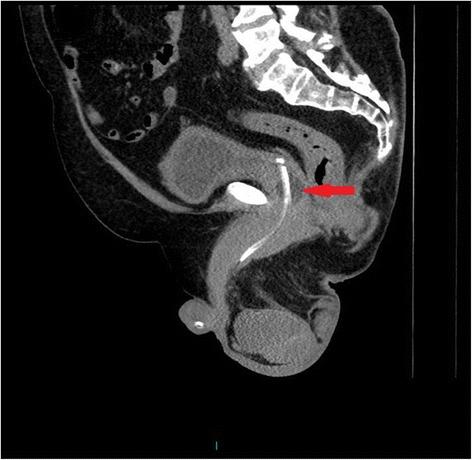

A tetraplegic patient started sweating profusely following insertion of a Foley catheter per urethra. The catheter was draining urine; there was no bypassing, no bleeding per urethra, and no haematuria. Patient's wife, who had been looking after her tetraplegic husband for more than forty years, told the health professionals that the catheter might have been placed incorrectly but her concerns were ignored. Ultrasound scan of urinary tract revealed no urinary calculi, no hydronephrosis. The balloon of Foley catheter was not seen in urinary bladder but this finding was not recognised by radiologist and spinal cord physician. Patient continued to sweat profusely; therefore, CT of pelvis was performed, but there was a delay of ten days. CT revealed the balloon of Foley catheter in the over-stretched prostate-membranous urethra; the tip of catheter was not located within the urinary bladder but was lying distal to bladder neck. Flexible cystoscopy was performed and Foley catheter was inserted into the bladder over a guide wire. The intensity of sweating decreased; noxious stimuli arising from traumatised urethra might take a long while to settle.